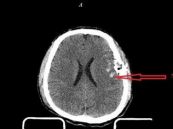

Dập não là một tổn thương chủ yếu trong chấn thương não nặng. Nếu nhẹ, dập não để lại di chứng về sau như động kinh. Nếu nặng, nó thường kèm theo phần lớn các máu tụ trong sọ. Để hiểu rõ hơn về bệnh, mời các bạn cùng tham khảo bài viết dưới đây nhé!

Xuất huyết trong não thất thường liên quan với máu tụ trong não, xuất huyết dưới màng nhện, máu tụ dưới màng cứng. Để biết rõ hơn về hội chứng này, eLip mời các bạn cùng tham khảo bài viết dưới đây nhé!